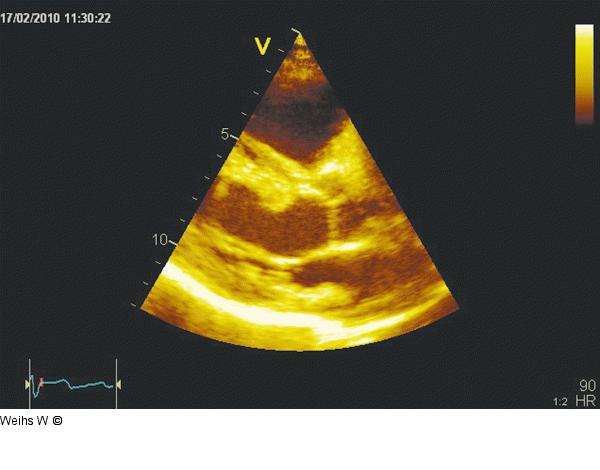

Abbildung 1: Transthorakale Echokardiographie Parasternaler Längsschnitt mit unauffälliger Darstellung des linken Ventrikels, der Mitral- und Aortenklappe sowie des linken Vorhofes. |

Abbildung 1: Transthorakale Echokardiographie

Parasternaler Längsschnitt mit unauffälliger Darstellung des linken Ventrikels, der Mitral- und Aortenklappe sowie des linken Vorhofes. |